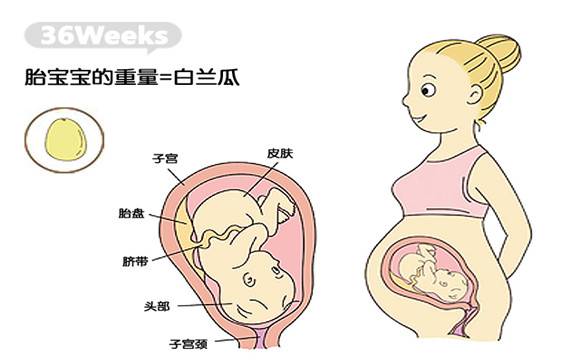

1.体重增加

专家提醒,怀孕36周时间阶段后,这个时候是胎儿体重增加最快的时候,可以说这个时候你的宝宝体重每天都在增加。有研究发现,怀孕36周的宝宝每天体重都能增加28克左右,而到了36周的周末这个时候你的宝宝已经可以算是足月儿了。一般情况下我们豆浆37~42周出生的宝宝称为足月宝宝,而在37周前出生的宝宝为早产儿,但是如果是在42周后出生的宝宝则为过期产儿。

2.胎脂脱落

怀孕36周时间后,这个时候的宝宝一般重量以2.7千克为主,并且身长约45~50厘米。除了体形方面有了明显的变化之外,专家还指出,这个时候覆盖宝宝全身的绒毛和在羊水中保护宝宝皮肤的胎脂也处于逐渐脱落的状态,并且这个时候的宝宝也已经会吞咽这些脱落的物质和其他分泌物了。像胎脂等脱落物质会积聚在宝宝的肠道里,知道他出生后才会排出。

3.身体发育完全

36周后的宝宝这个时候随时都做好冲出母体的准备,因此胎儿的姿势很可能是头冲下的,这是顺产的最理想姿势。不仅做好了出生的准备,同时这个时候宝宝的身体各个身体发育也基本完善了,比如指甲又长长了而且还有可能会超过指尖,还有就是两个肾脏已发育完全。除此之外这个时候胎儿的肝脏器官也已经能够处理一些代谢废物了。而且宝宝的脾脏发育完成,并可以分泌胰岛素了。

这个时候的宝宝如果在你腹中活动的话,他的手肘、小脚丫和头部可能会清楚地在你的腹部突现出来,这是由于这个时候子宫壁和腹壁已变得很薄了。这部分也是孕36周胎儿发育情况,孕妈妈应该了解。